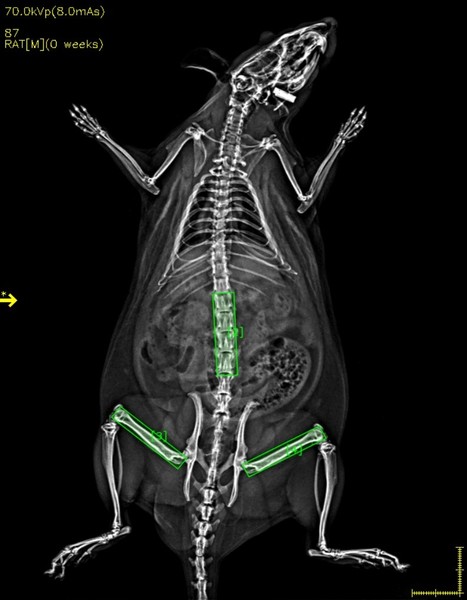

用超高分辨X射线成像方法对活体大、小鼠等实验动物、离体的组织、骨骼样本、脏器样本进行高分辨率的X光成像,

可同时得到样本整体以及相应ROI区域的骨矿含量(BMC),骨密度(BMD),脂肪含量(Fat),肌肉含量(Lean),等数值;

可对ROI区域区域,如椎体、股骨、胫骨、皮下脂肪、脏器脂肪等进行单独分析

| ROI | BMD | BMC | 骨骼区域 | 组织区域 | 脂肪(%) | 脂肪(g) | 肌肉(g) | 总重 |

| ROI1 | 0.061 | 0.636 | 10.478 | 22.362 | 27.35 | 10.435 | 27.718 | 38.789 |